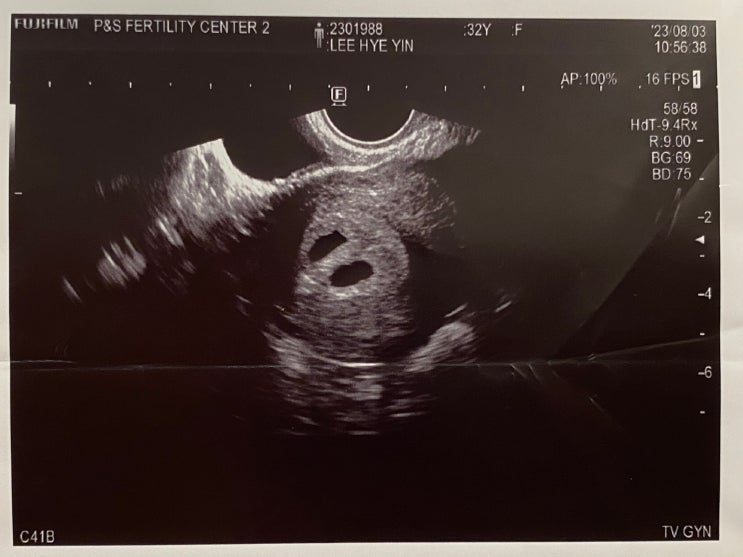

감자와눈사람 아기집 확인 / 시험관 총 비용

8/10(목) 심장소리 확인 아기집 확인 하고 1주일 만에 다시 병원 방문 이번에는 심장소리 확인하러 왔다 두...